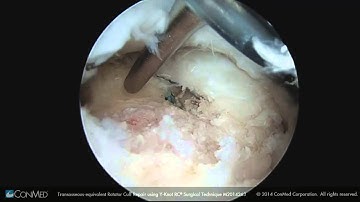

ConMed Linvatec Spectrum® MVP™ Suture Passer Overview